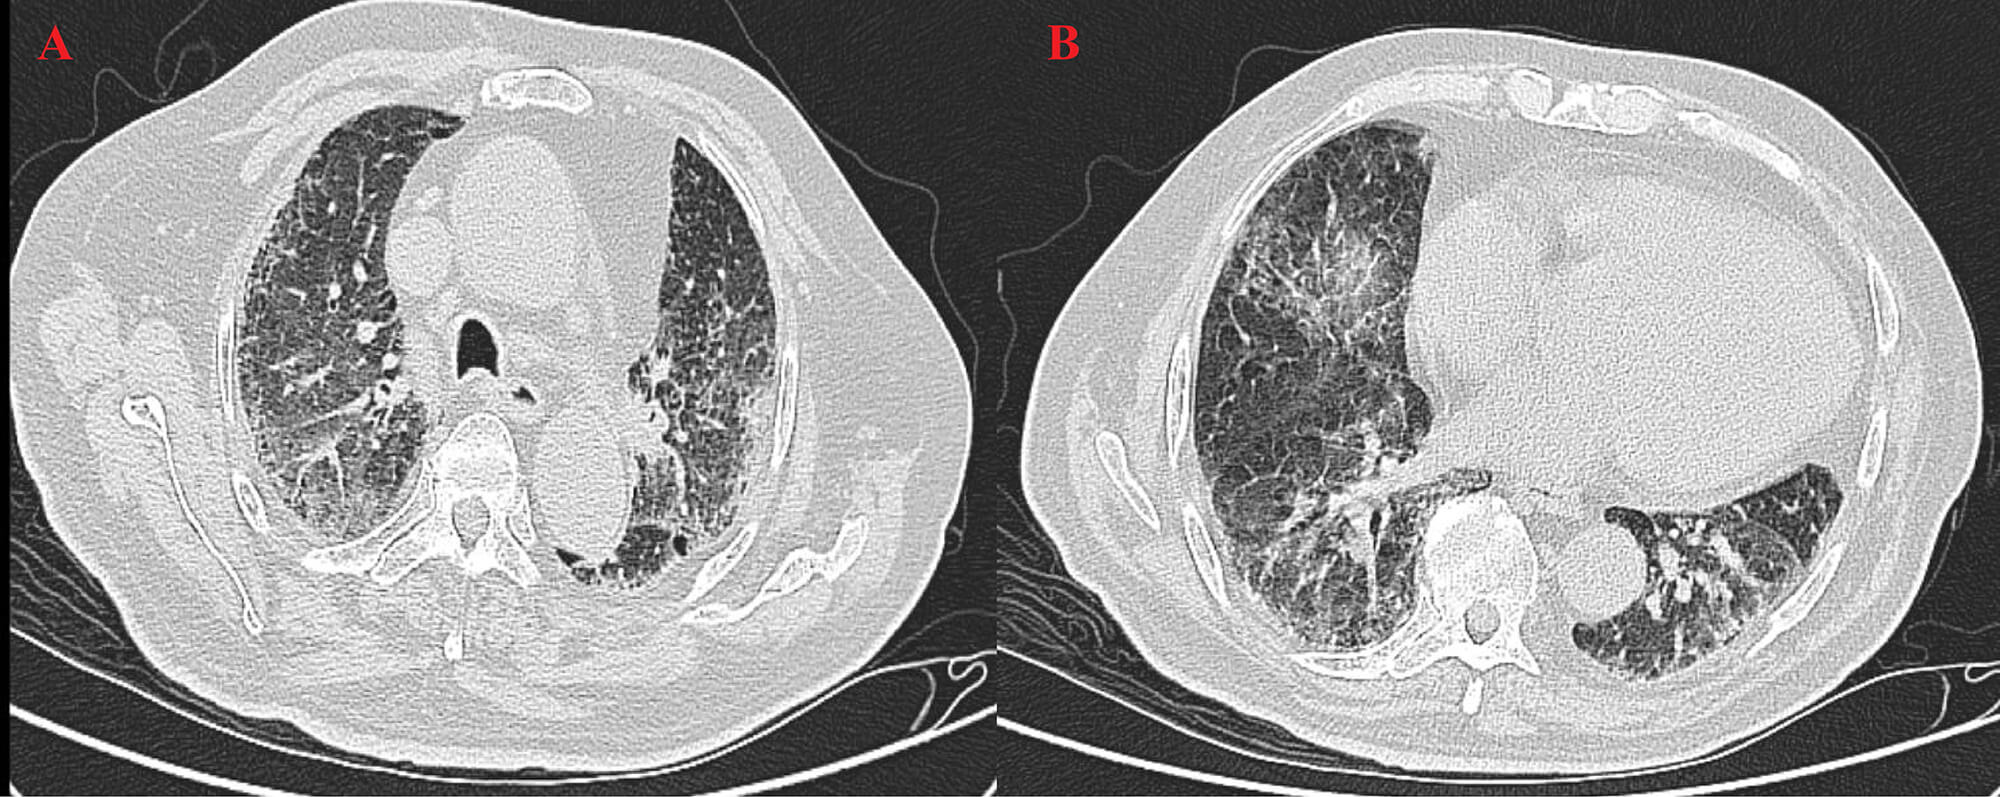

High-resolution computed tomography (HRCT) (Fig. 3) revealed patchy opacities in the left upper and right lower lobes, accompanied by multiple enlarged hilar and mediastinal lymph nodes (Fig. 4), interstitial inflammation in both lungs (Fig. 5), and a small pleural effusion. These findings were consistent with residual tumor and local progression following treatment for extensive-stage SCLC, demonstrating characteristic imaging features of SCLC.

Fig. 5.

HRCT on 22 August 2025. (A) The left upper lobe shows fibrotic changes and partial absorption, indicating post-treatment improvement. (B) The right lower lobe shows persistent high-density areas and mild pleural effusion, indicating residual inflammation and need for follow-up.